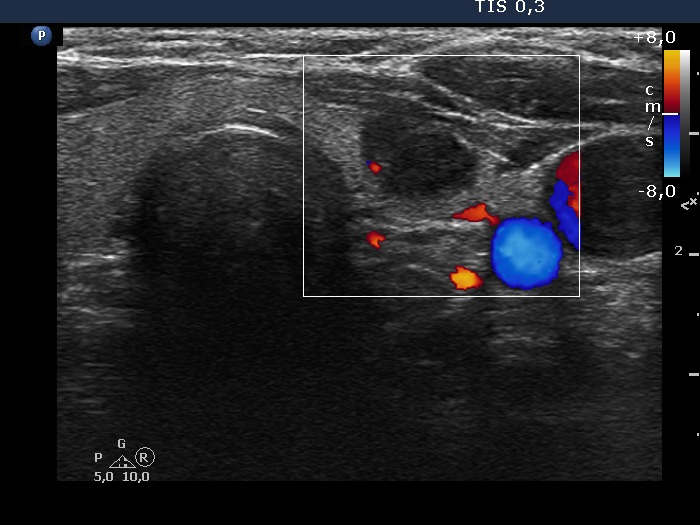

The borders of the nodule - case 2104 (ultrasonographic picture 5)

Five months after the first examination

Left lobe, transverse scan, color Doppler mode. The vascularization is not specific.